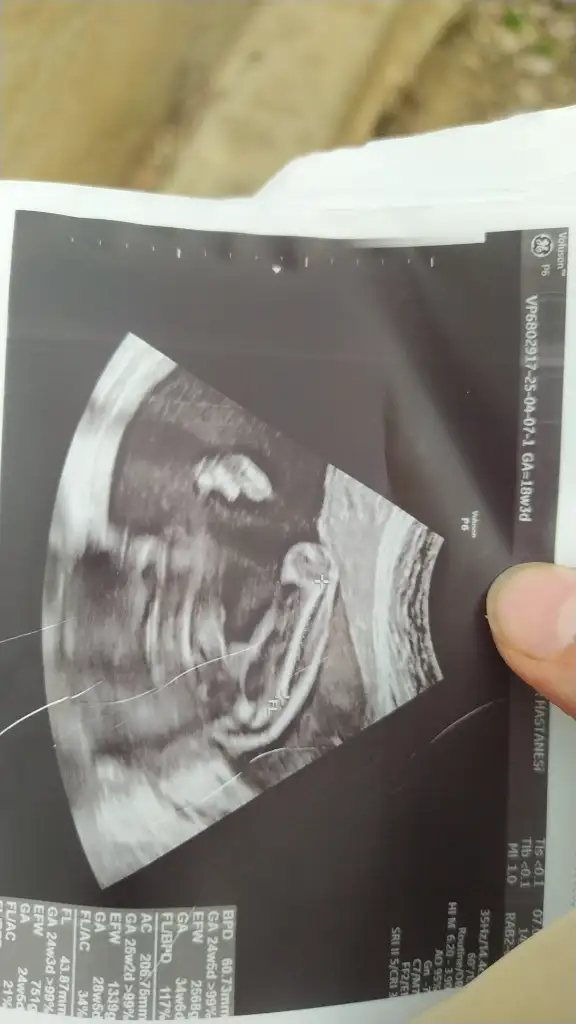

Bunlarada bakar mısınız lütfenErkek canım

Bunlarada bakar mısınız lütfenEvet erkek bu bebiş

Bunlarada bakar mısınız lütfenNub teorisi benim 2 oğlumda doğru çıktı. Bu bebiş kıza benziyor

Nub teorisi benim 2 oğlumda doğru çıktı. Bu bebiş kıza benziyor